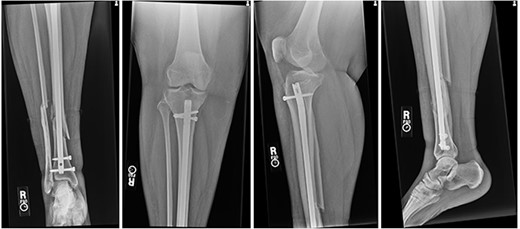

At 2 weeks post-op, the patient was managing pain well, and she demonstrated appropriate range of motion and strength. At 6-week follow-up, however, she complained of diffuse, painful grinding in the right knee which impaired her ability to ambulate. Physical exam revealed audible and palpable crepitus in the knee as well as tenderness to palpation at the medial and lateral joint lines. Radiographs demonstrated unchanged alignment of the tibia fracture (Fig. 3). Multiplanar T1 and T2 MRI without contrast revealed a large full-thickness defect on the lateral femoral trochlea measuring 1.8 cm in diameter with a loose chondral fragment in the superior medial joint space (Fig. 4).

Radiographs at 6 weeks post-op demonstrating unchanged alignment of the distal tibia/fibula fracture.